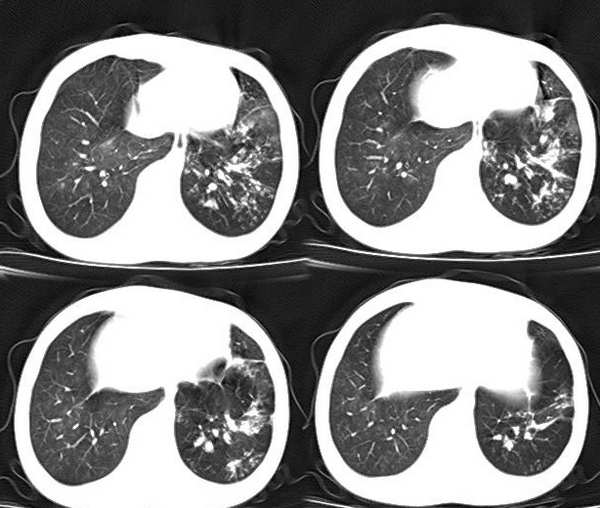

以下是引用x线在2006-2-2 17:37:00的发言:[br]结合病史支持“ct拟诊:双侧tb,左下叶结核球,左下叶局限性轻度支扩。”双下叶及左舌叶淡薄的毛玻璃密度影,我考虑为炎性渗出。另:是否合并霉菌感染须进一步检查确定。